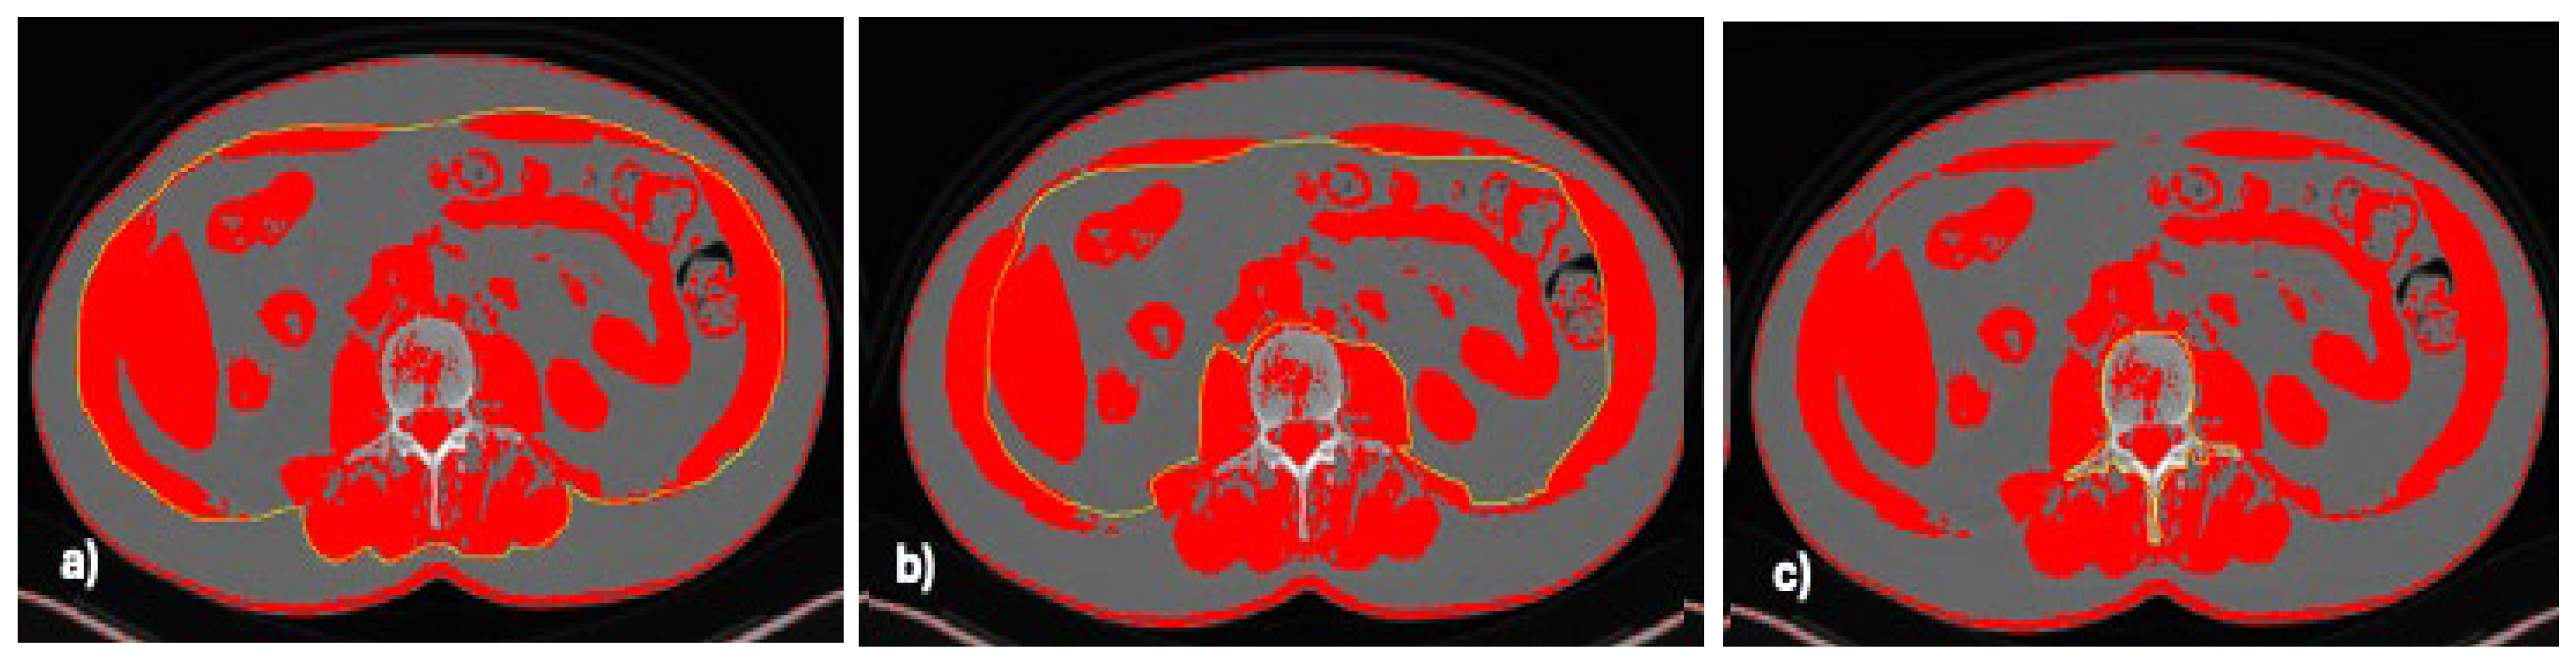

- Available online: https://imagej.net/ij/nih-image (accessed on 15 April 2024).

- Gomez-Perez, S.L.; Haus, J.M.; Sheean, P.; Patel, B.; Mar, W.; Chaudhry, V.; McKeever, L.; Braunschweig, C. Measuring Abdominal Circumference and Skeletal Muscle from a Single Cross-Sectional Computed Tomography Image: A Step-by-Step Guide for Clinicians Using National Institutes of Health ImageJ. JPEN J. Parenter. Enter. Nutr. 2016, 40, 308–318. [Google Scholar] [CrossRef] [PubMed]

- Gomez-Perez, S.; McKeever, L.; Sheean, P. Tutorial: A Step-by-Step Guide (Version 2.0) for Measuring Abdominal Circumference and Skeletal Muscle from a Single Cross-Sectional Computed-Tomography Image Using the National Institutes of Health ImageJ. JPEN J. Parenter. Enter. Nutr. 2020, 44, 419–424. [Google Scholar] [CrossRef] [PubMed]